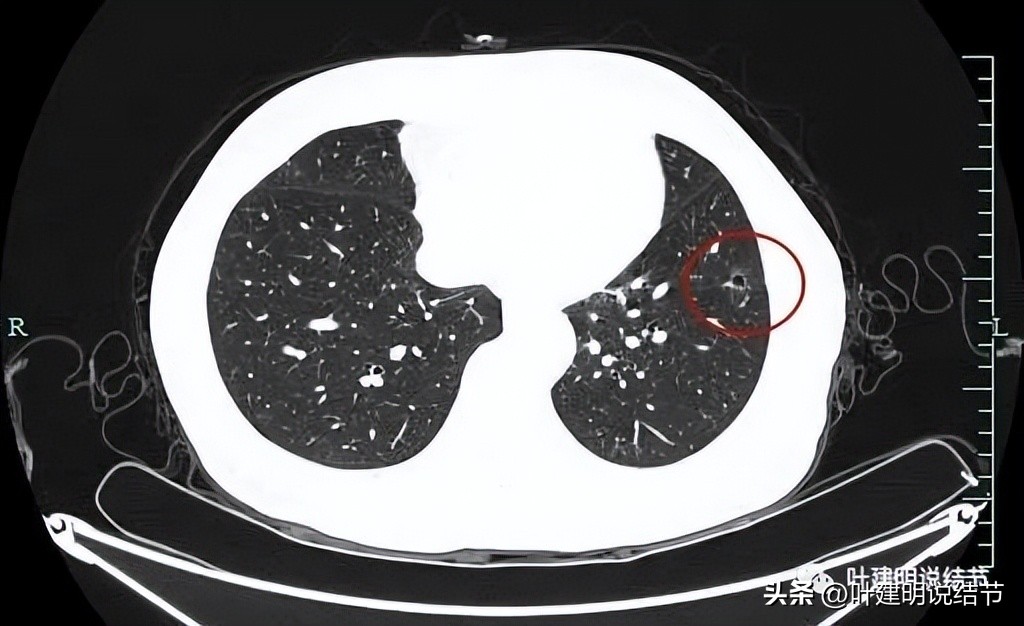

病灶轮廓清,中间有实性成分,磨玻璃部分瘤肺边界清,表面也不平,考虑肿瘤可能性大。

病灶仍是囊腔型,壁不均,表面不平,部分囊壁密度略高。

左下这个囊腔型病灶进展是没有明显进展的,但确实有磨玻璃成分、有血管进入,整体轮廓较清。感觉恶性的可能性大些,反正位置好,在边缘部位,单孔局部楔形切了化验也可以的,也比较稳当些。

再看左下叶的主病灶,此层见其是磨玻璃密度,轮廓较清,内部密度欠均匀。

有明显血管征,血管进入后有分支发出,病灶表面显得有毛刺样。

病灶中间有空腔。

囊壁较薄,但不均匀,有的地方还是显略厚了点的。